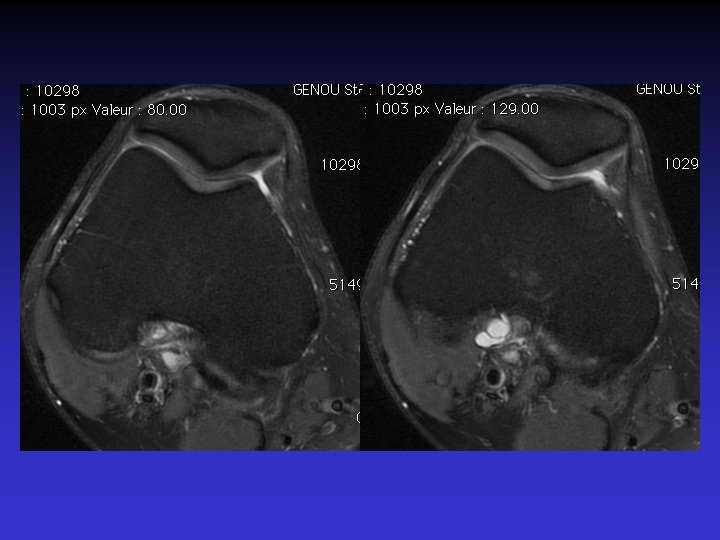

ATTEINTE BILATERALE • Non exceptionnelle • Concomitante ou décalée dans le temps

Mme S… 60 ANS DROIT

Mme S… 60 ANS GAUCHE